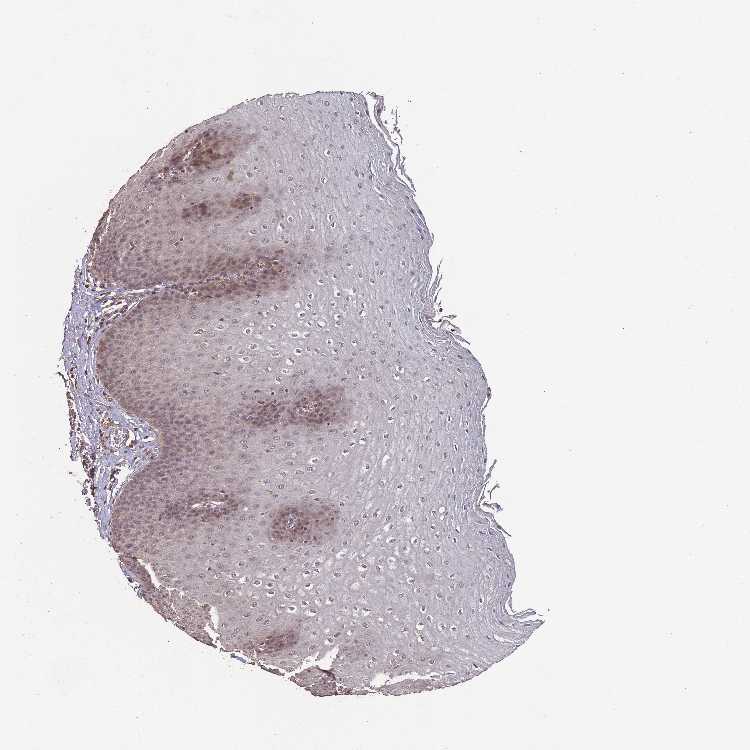

ESOPHAGUS - Antibody stainingi

Antibody staining in the annotated cell types in the current human tissue is reported as not detected, low, medium, or high, based on conventional immunohistochemistry profiling in selected tissues. This score is based on the combination of the staining intensity and fraction of stained cells.

Each image is clickable and will lead to virtual microscopy that enables deeper exploration of all samples and also displays staining intensity scores, fraction scores and subcellular localization as well as patient and tissue information for each sample.

Antibody CAB046472

Squamous epithelial cells Low